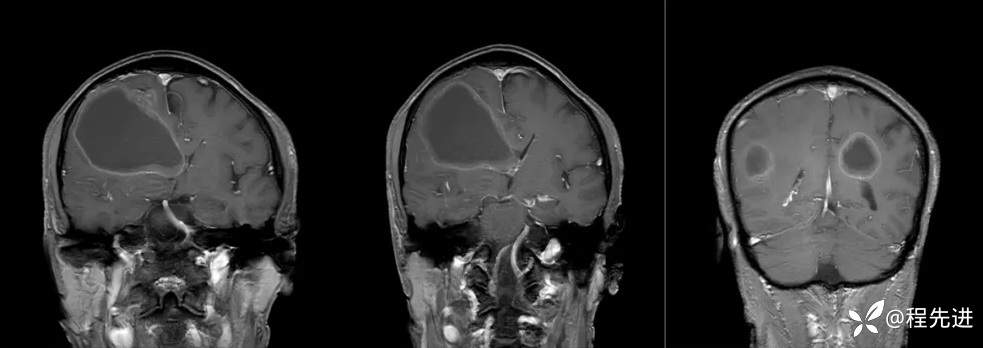

患者性别:男

患者年龄:65岁

简要病史:头痛、神志异常、行走不稳3周

实验室检查:未见明显异常

MRI平扫+增强:

T1增强: